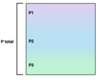

Match the lung volumes and capacities to the corresponding letters in the image.

Inspiratory reserve volume

Inspiratory capacity

Functional residual capacity

Vital capacity

A

B

C

D

Inspiratory reserve volume + A

Functional residual capacity + B

Inspiratory capacity + C

Vital capacity + D